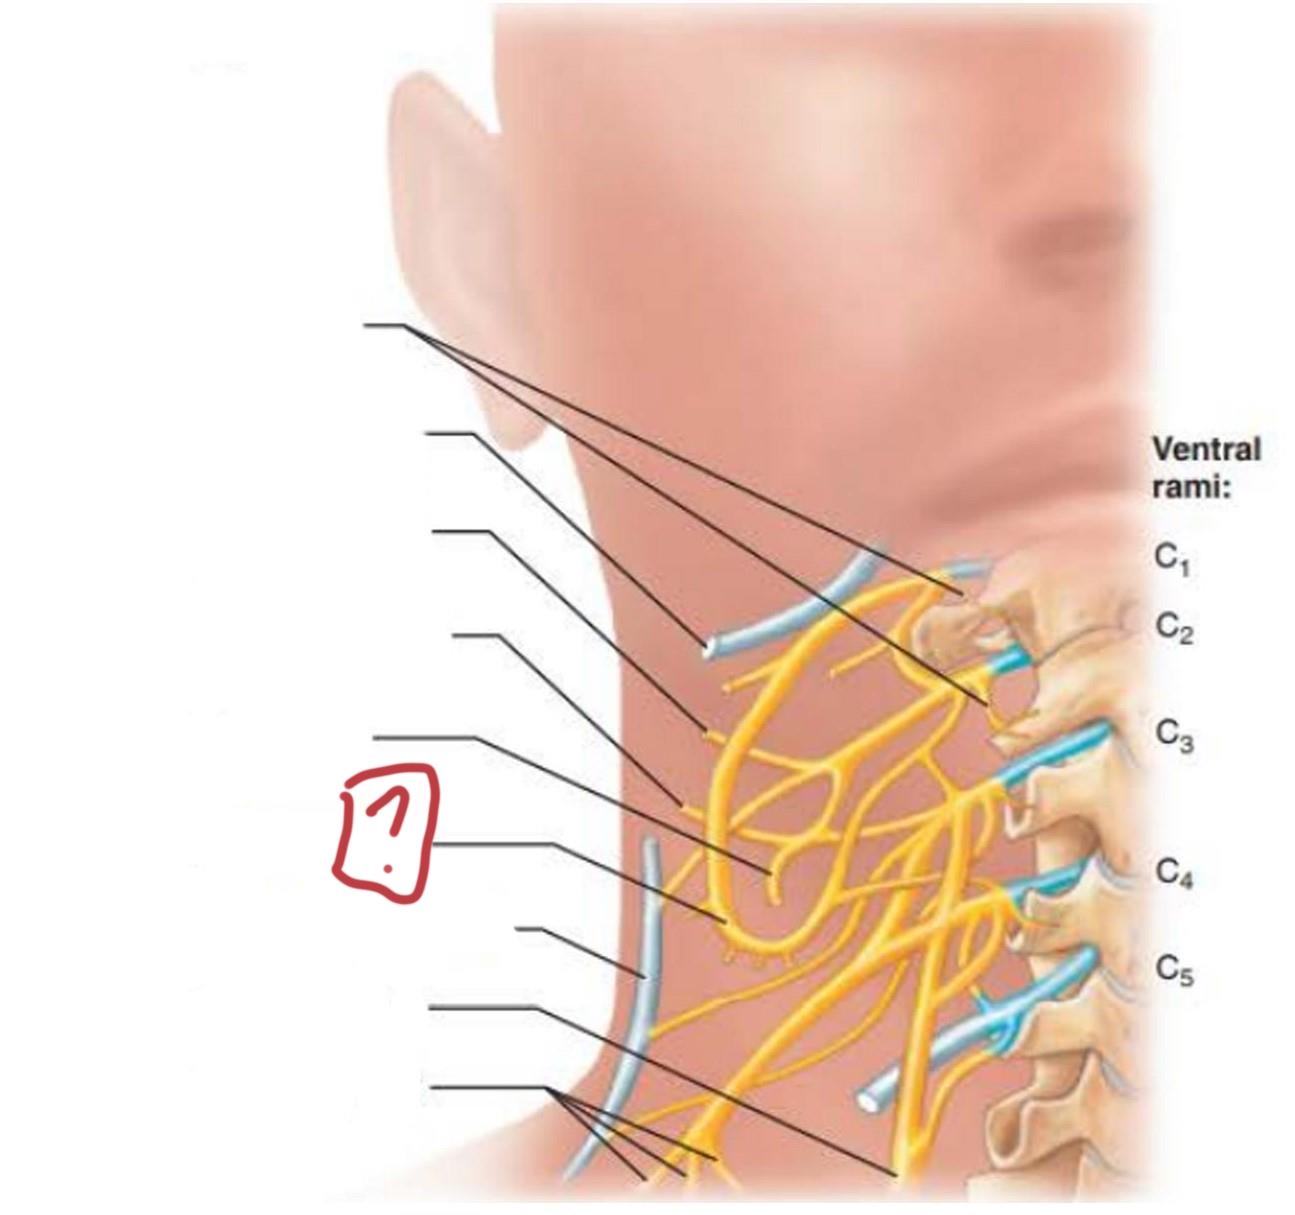

cervical plexus

C1-C4

segmental branches

hypoglossal nerve (12)

lesser occipital nerve

greater auricular nerve

transverse cervical nerve

ansa cervicalis

accessory nerve (11)

phrenic nerve

supraclavicular nerves